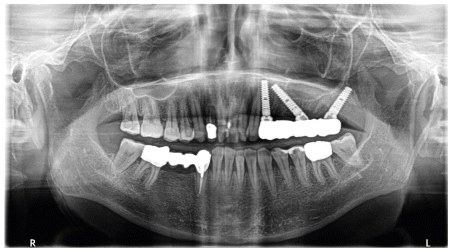

Implant site preparation was done using dedicated drills with increasing diameter, with constant irrigation using physiological saline solution to remove bone debris. Subsequently, a Winsix K25 straight implant (3.8 mm diameter, 15 mm length) was inserted at site 2.4, along with the two 35° tilted Winsix K25 implants (3.8 mm diameter, 15 mm length) at sites 2.6 and 2.7. All implants achieved an insertion torque greater than 30 Ncm.

The Winsix abutments were then placed, the flap was sutured, and the pre-The fabricated screw-retained prosthetic framework was positioned immediately.

Subsequent follow-up visits confirmed complete healing of the surgical wound and successful osseointegration of all three implants. This allowed for The delivery of the definitive prosthetic rehabilitation three months after the surgical intervention.